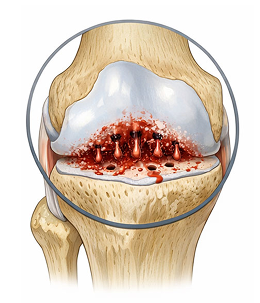

퇴행성관절염이란?

Degenerative arthritis퇴행성관절염은 연골이 반복적인 자극과 노화로 인해 손상되면서 염증과 통증을 유발하고,

결국 움직임에 제한을 가져오는 질환입니다.

다양한 요인으로 연골에 지속적인 자극이 가해지면서 관절을 보호하는 능력이 크게 감소하게 됩니다.

정상적인 모습

환자의 모습